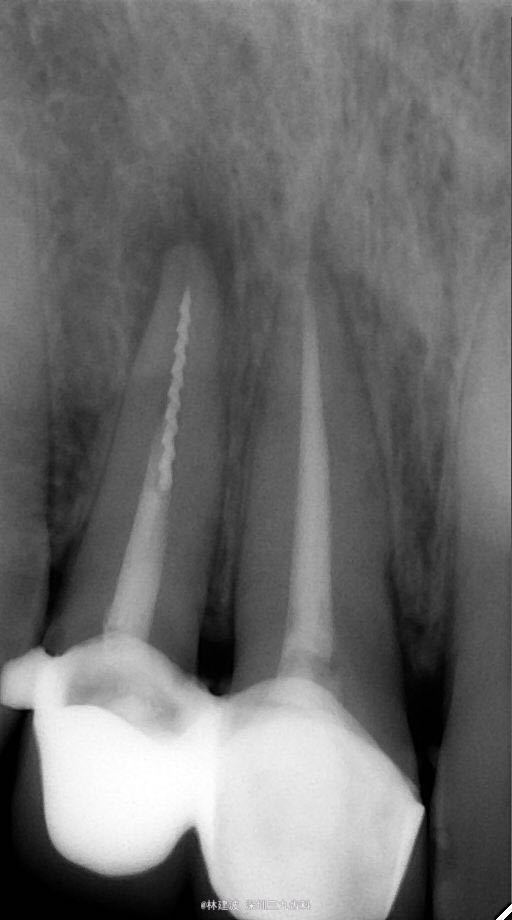

诊断 处理

显微镜下超声器械取出折断的根管锉,再次根预备封药。